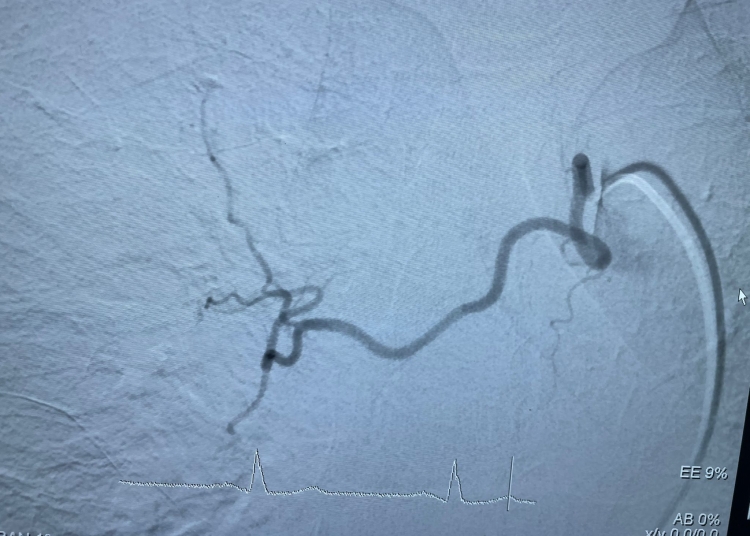

Investigația prin tomografie computerizată a relevat un focar subsegmentar de hemoragie alveolară, situat în apropierea unei formațiuni tisulare pulmonare din segmentul posterior al lobului superior drept. După evaluare, medicii au hotărât să efectueze o embolizare cu particule a arterei bronșice drepte, o procedură minim invazivă care implică blocarea fluxului de sânge către zona afectată pentru a opri sângerarea.

Intervenția s-a dovedit a fi un succes, pacientul înregistrând o ameliorare semnificativă a hemoptiziei în zilele următoare. Această realizare medicală întărește poziția Spitalului Clinic Județean de Urgență Constanța ca un centru de referință regional în domeniul radiologiei intervenționale, subliniind importanța colaborării între specialități precum pneumologia, imagistica și chirurgia endovasculară.